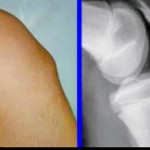

■ オスグッド病(膝の痛み)

正式名称は オスグッド・シュラッター病。

大腿四頭筋の牽引力により、脛骨粗面が炎症を起こす状態です。